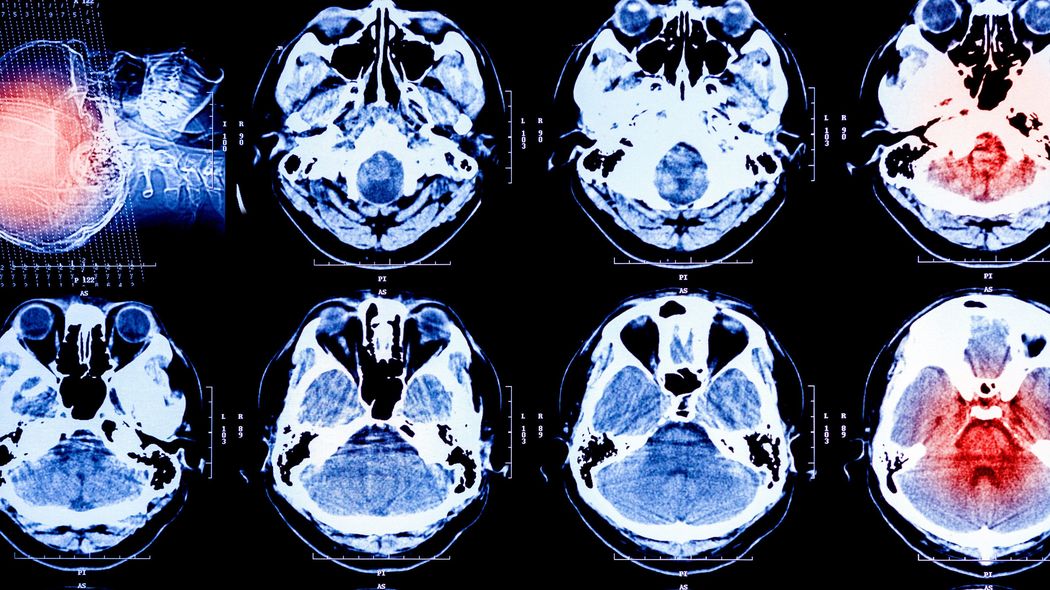

CTや血液検査を行った後、医師が「前から口って曲がってました? もしかしたら脳梗塞かもしれないのでMRI撮りますね」と言う。

結果はやはり脳梗塞だった。